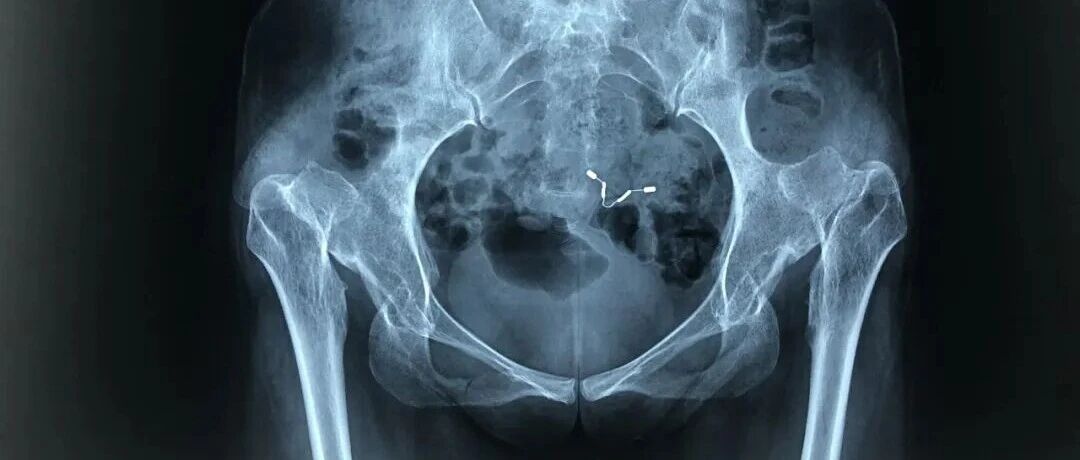

![]() 这么年轻,就把两个关节给换了,合适吗? 刀客居 发布时间2026/01/16 23:44:29 | 63 | - | - | 197 | 更多 |